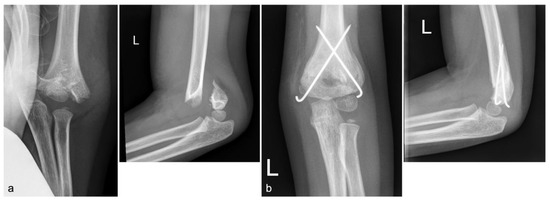

A Modified Technique for Medial Pin Placement in Pediatric Supracondylar Humerus Fractures

Background: Displaced pediatric supracondylar humerus fractures (PSHFs) commonly require surgical treatment. Medial pin placement can cause iatrogenic ulnar nerve injury. This study presents a modified, step-by-step cross-pinning technique for PSHFs designed to avoid iatrogenic ulnar nerve injury. Methods: We retrospectively included [...] Read more.

Background: Displaced pediatric supracondylar humerus fractures (PSHFs) commonly require surgical treatment. Medial pin placement can cause iatrogenic ulnar nerve injury. This study presents a modified, step-by-step cross-pinning technique for PSHFs designed to avoid iatrogenic ulnar nerve injury. Methods: We retrospectively included patients with PSHF (Gartland types III or IV) who underwent closed reduction and percutaneous cross-pinning at our hospital from June 2014 to December 2024. Demographic data, fracture type, and preoperative and postoperative neurological deficits were recorded. Results: A total of 40 patients (16 boys and 24 girls) with a mean age of 6.6 ± 2.2 years (range, 2–14) were included. Most injuries were type III (35/40; 87.5%), whereas five patients (12.5%) had type IV injuries. Our technique resulted in no new cases of postoperative ulnar neuropathy. Conclusions: This study describes a modified medial pin insertion technique for unstable PSHFs. Careful attention to medial pin placement can minimize iatrogenic ulnar nerve injury. Full article